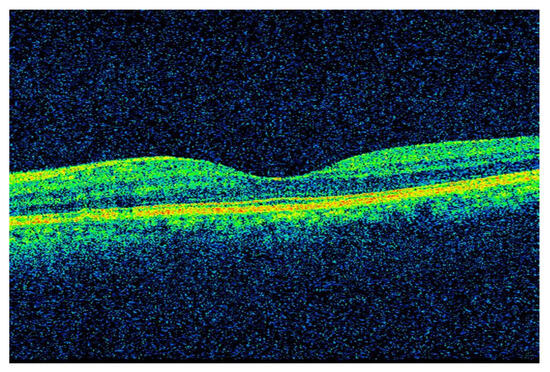

3.1. Retinal Layer Segmentation and Thickness Computation